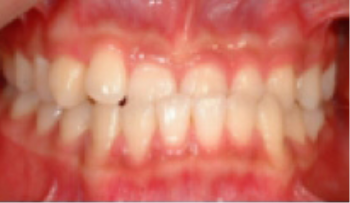

교정 치료 Before&After

• 총생(Crowding) 치아가 삐뚤게 남.

Before

After